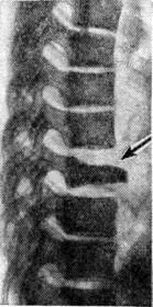

Остеохондропатия тела позвонка развивается в результате нарушения его кровоснабжения, причины которого не ясны. Поражается один позвонок в нижнегрудном или верхнепоясничном отделах позвоночника. Первым и основным симптомом является постепенно нарастающая боль в области поражённого позвонка. При пальпации позвоночника отмечается локальная болезненность, ограниченное напряжение мышц и небольшое выступание остистого отростка поражённого позвонка. Общая или местная температурная реакция и изменения в гемограмме отсутствуют. Рентгенологическое симптомокомплекс — платибрахиспондилия, то есть уплощение тела позвонка и его расширение. Высота тела позвонка снижается как в переднем, так и в заднем отделах, и он приобретает вид узкой полоски, выступающей кпереди на несколько миллиметров (рисунок). Межпозвонковые диски в этом участке расширены.

Рис

Рентгенограмма грудного отдела позвоночника в боковой проекции. Остеохондропатия тела позвонка (болезнь Кальве): стрелкой указан поражённый позвонок.